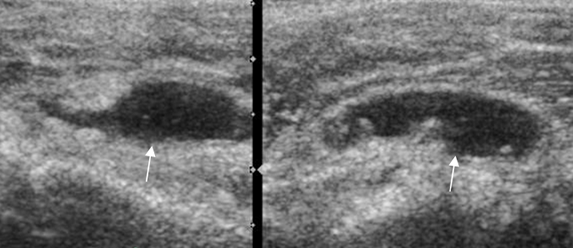

Fig 142. Bursitis subacromial.

Ecografía coronal. Colección líquida irregular y con ecos internos sobre la bursa SASD,

por bursitis.